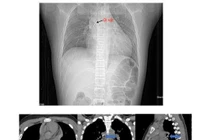

Theo đó, bệnh nhân nữ 67 tuổi nhập viện vì ho kéo dài, đau ngực âm ỉ. Qua nội soi phế quản, các bác sĩ tại khoa Thăm dò chức năng - Nội soi đã phát hiện một hạt hồng xiêm mắc sâu ở thùy dưới phổi phải, gây tắc nghẽn và viêm phổi kéo dài. Nhờ can thiệp nội soi phế quản, dị vật được lấy ra an toàn và bệnh nhân hồi phục tốt.

hat-hong-xiem.jpg

Ê-kíp phẫu thuật nội soi lấy dị vật cho bệnh nhân - Ảnh BVCC